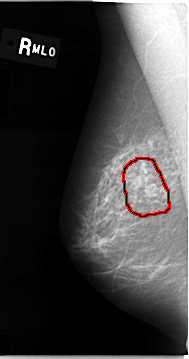

C_0010_1.RIGHT_MLO

RIGHT_MLO LINES 4656 PIXELS_PER_LINE 2456 BITS_PER_PIXEL 12 RESOLUTION 50 OVERLAY

FILE: C_0010_1.RIGHT_MLO.OVERLAY

TOTAL_ABNORMALITIES 1

ABNORMALITY 1

LESION_TYPE CALCIFICATION TYPE PLEOMORPHIC DISTRIBUTION CLUSTERED

ASSESSMENT 5

SUBTLETY 5

PATHOLOGY MALIGNANT

TOTAL_OUTLINES 1

BOUNDARY